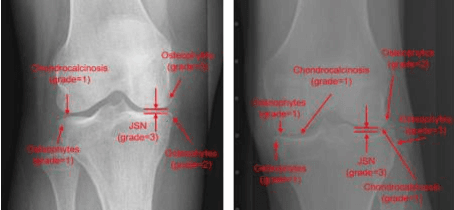

Abstract:Osteoarthritis (OA) poses a global health challenge, demanding precise diagnostic methods. Current radiographic assessments are time consuming and prone to variability, prompting the need for automated solutions. The existing deep learning models for OA assessment are unimodal single task systems and they don't incorporate relevant text information such as patient demographics, disease history, or physician reports. This study investigates employing Vision Language Processing (VLP) models to predict OA severity using Xray images and corresponding reports. Our method leverages Xray images of the knee and diverse report templates generated from tabular OA scoring values to train a CLIP (Contrastive Language Image PreTraining) style VLP model. Furthermore, we incorporate additional contrasting captions to enforce the model to discriminate between positive and negative reports. Results demonstrate the efficacy of these models in learning text image representations and their contextual relationships, showcase potential advancement in OA assessment, and establish a foundation for specialized vision language models in medical contexts.